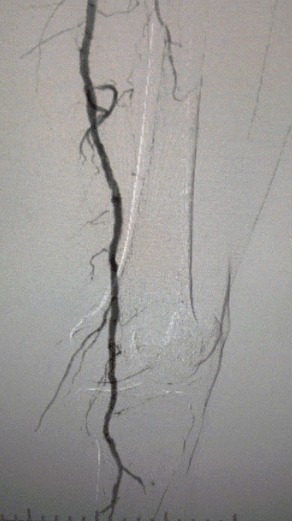

Los hallazgos clínicos

· Examen físico: Pulsos femorales débiles; ausencia de pulsos poplíteo y dorsalis pedis; ulceración en el primer dedo del pie izquierdo; necrosis en el primer y segundo dedo del pie derecho

· Imagen preoperatoria: estenosis calcificada difusa y grave en arterias bilaterales de las extremidades inferiores

Resultado quirúrgico

Después del procedimiento, la estenosis arterial mejoró significativamente, el flujo sanguíneo aumentó y la temperatura de la piel aumentó. No hubo complicaciones postoperatorias. Tanto el paciente como el equipo quirúrgico estaban muy satisfechos con los resultados.